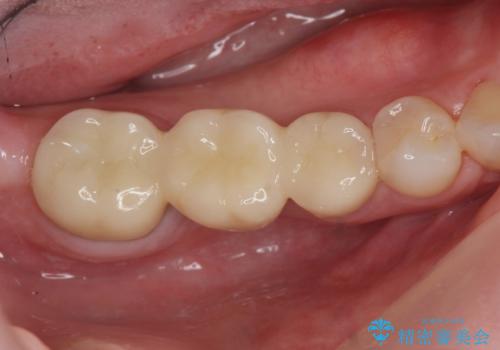

放置した虫歯 ブリッジ治療

- 治療途中の歯を3年放置した結果、ファイバーコア下に虫歯が再発し抜歯を余儀なくされました。

インプラント治療ではなく手術の必要のないブリッジ治療を希望・選択されたので治療を進めます。

- 36.3万円(仮歯・ジルコニアクラウン×3)費用は治療当時の料金となります